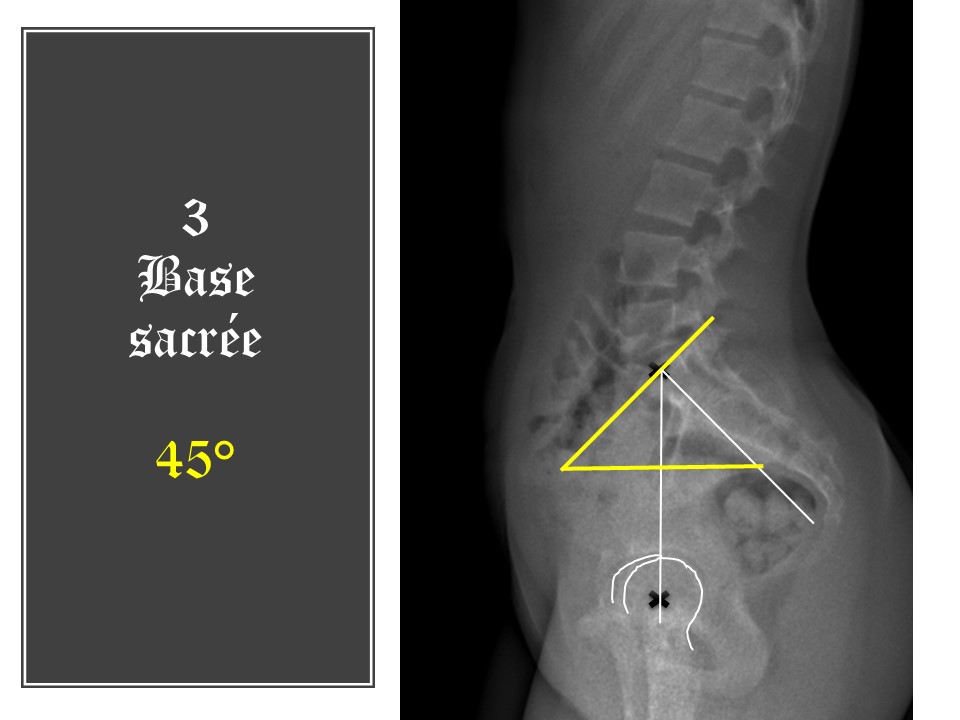

La pente sacrée est calculée par rapport à l'horizontale. Ici 45°. L'inclinaison de la pente sacrée gère la répartition de la charge entre le corps vertébral en avant et l'arc postérieur en arrière. La meilleure répartition est obtenue à 37°.

L'incidence pelvienne est égale à la somme de l'inclinaison pelvienne et de la pente sacrée (PI=PT+SS). La bascule du bassin est donc ici de 3°, ce qui confirme l'antéversion du bassin. Compte tenu de l'incidence pelvienne, la bascule pelvienne devrait être de 10°. Il y a donc une anomalie de la statique dans le plan sagittal.